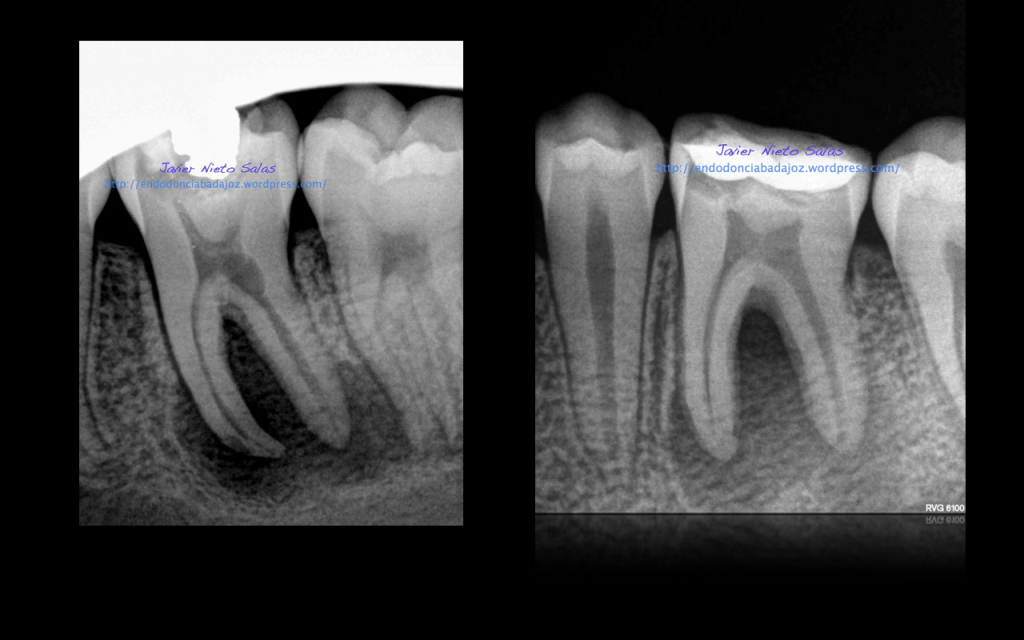

Se trata de un par de molares inferiores con lesiones apicales (Periodontitis apicales crónicas ). Consecuencia de caries profundas en su momento.

Se tratan del caso A y el caso B, por orden de posición, ambos casos se instrumentaron de la misma manera, elegimos Protaper hasta una F2, ambos casos se realizaron en una sesión tras abundante irrigación y finalmente se obturaron con condensación Vertical con la técnica de Ola continua de Buchanan complementando en el backfilling con guatpercha inyectada con la Pistola Obtura II.

Caso A:

Llamamos a la paciente a revisión a los 10 meses: